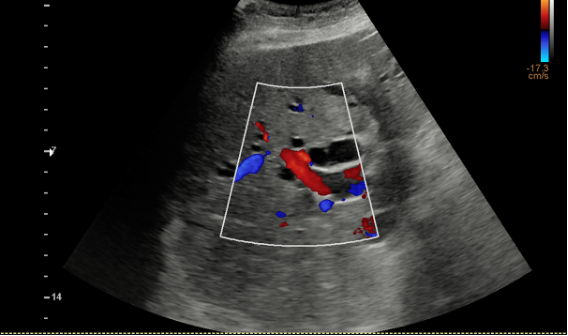

Hallazgos ecográficos